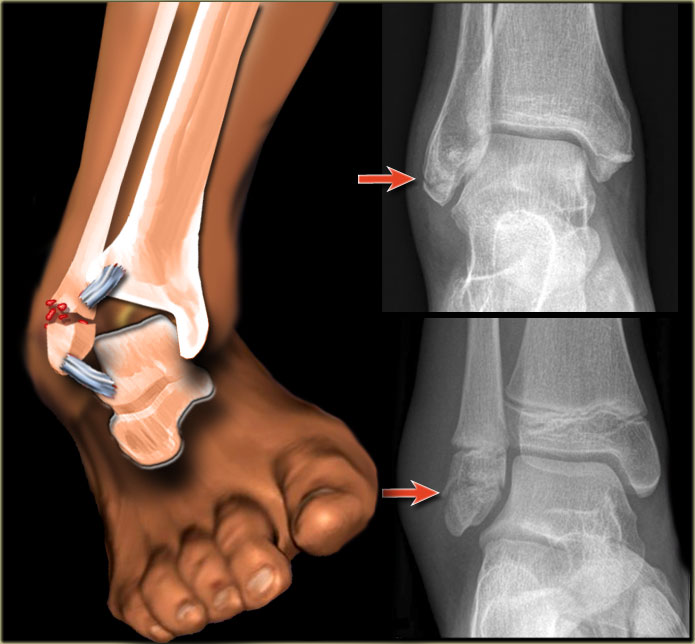

- разрывы связок лодыжки.

Для выбора метода лечения необходима диагностика. Пациенту рекомендуется пройти рентгенографию или МРТ лодыжки. Полученные изображения анализируются хирургом или травматологом для точной диагностики и определения необходимости операции. При выборе хирургического вмешательства пациенту также назначаются анализы крови и мочи, а также проводится оценка риска аллергических реакций на анестезирующие препараты.